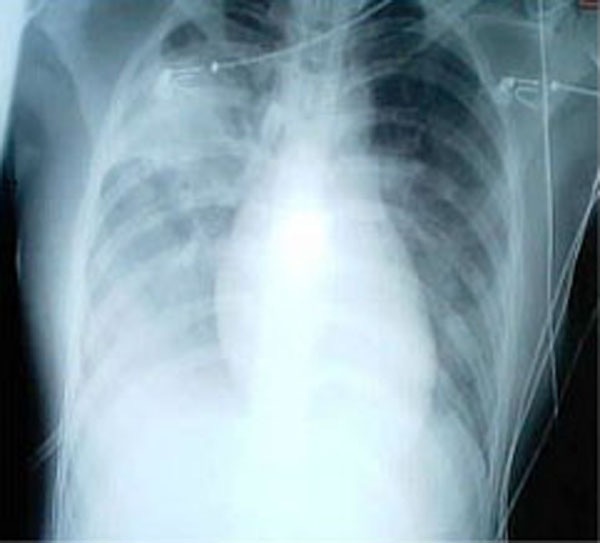

SARS感染的肺部